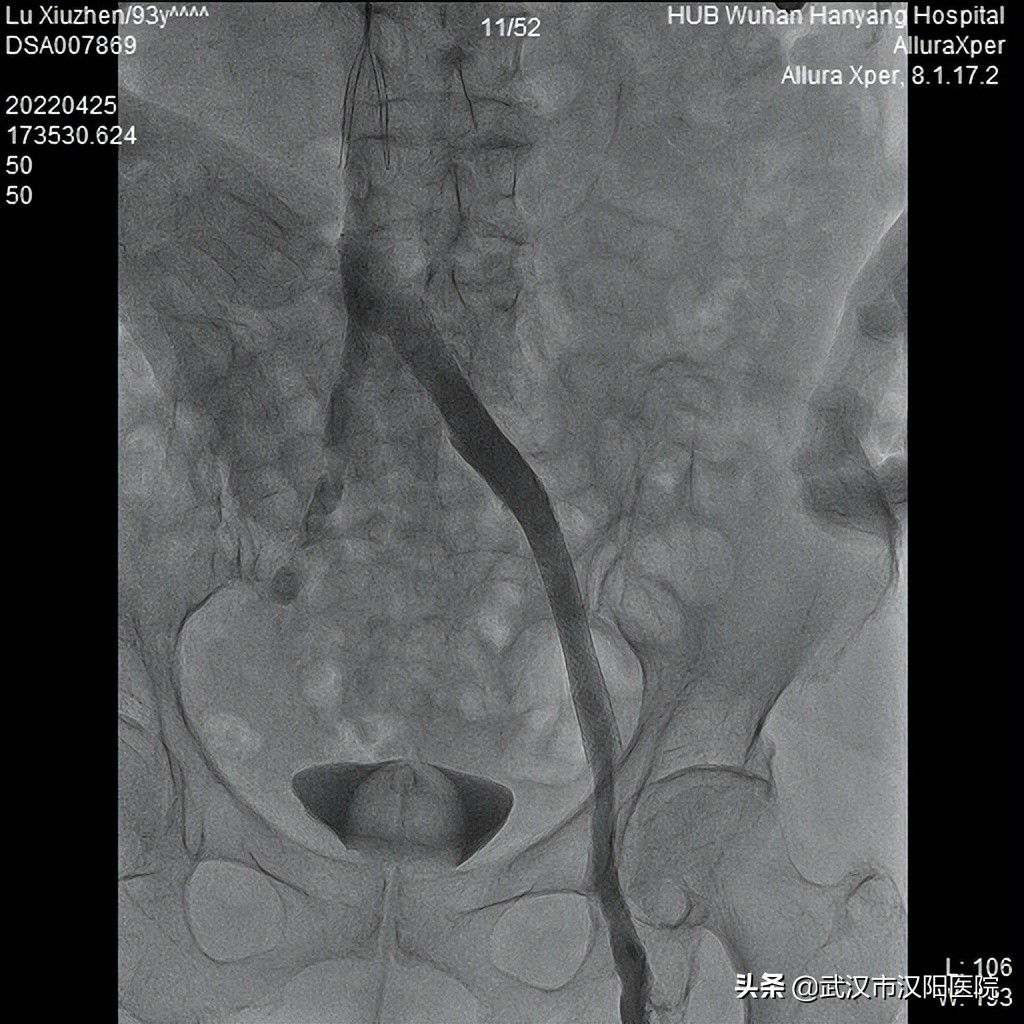

图3:做了血栓抽吸、髂静脉支架后,髂静脉显影好

手术中仅花费280秒即完成微创的血栓抽吸治疗,股腘静脉基本恢复通畅,但髂静脉明显狭窄,导致病人左下肢还有肿胀症状,又用半小时行髂静脉球囊扩张支架植入术,卢奶奶在手术台上左下肢就明显松软了,手术过程十分顺利。仅仅入导管室不到1小时,出来后她的腿就明显消肿了。

图4:最后一次造影结果,髂股腘静脉都显影了